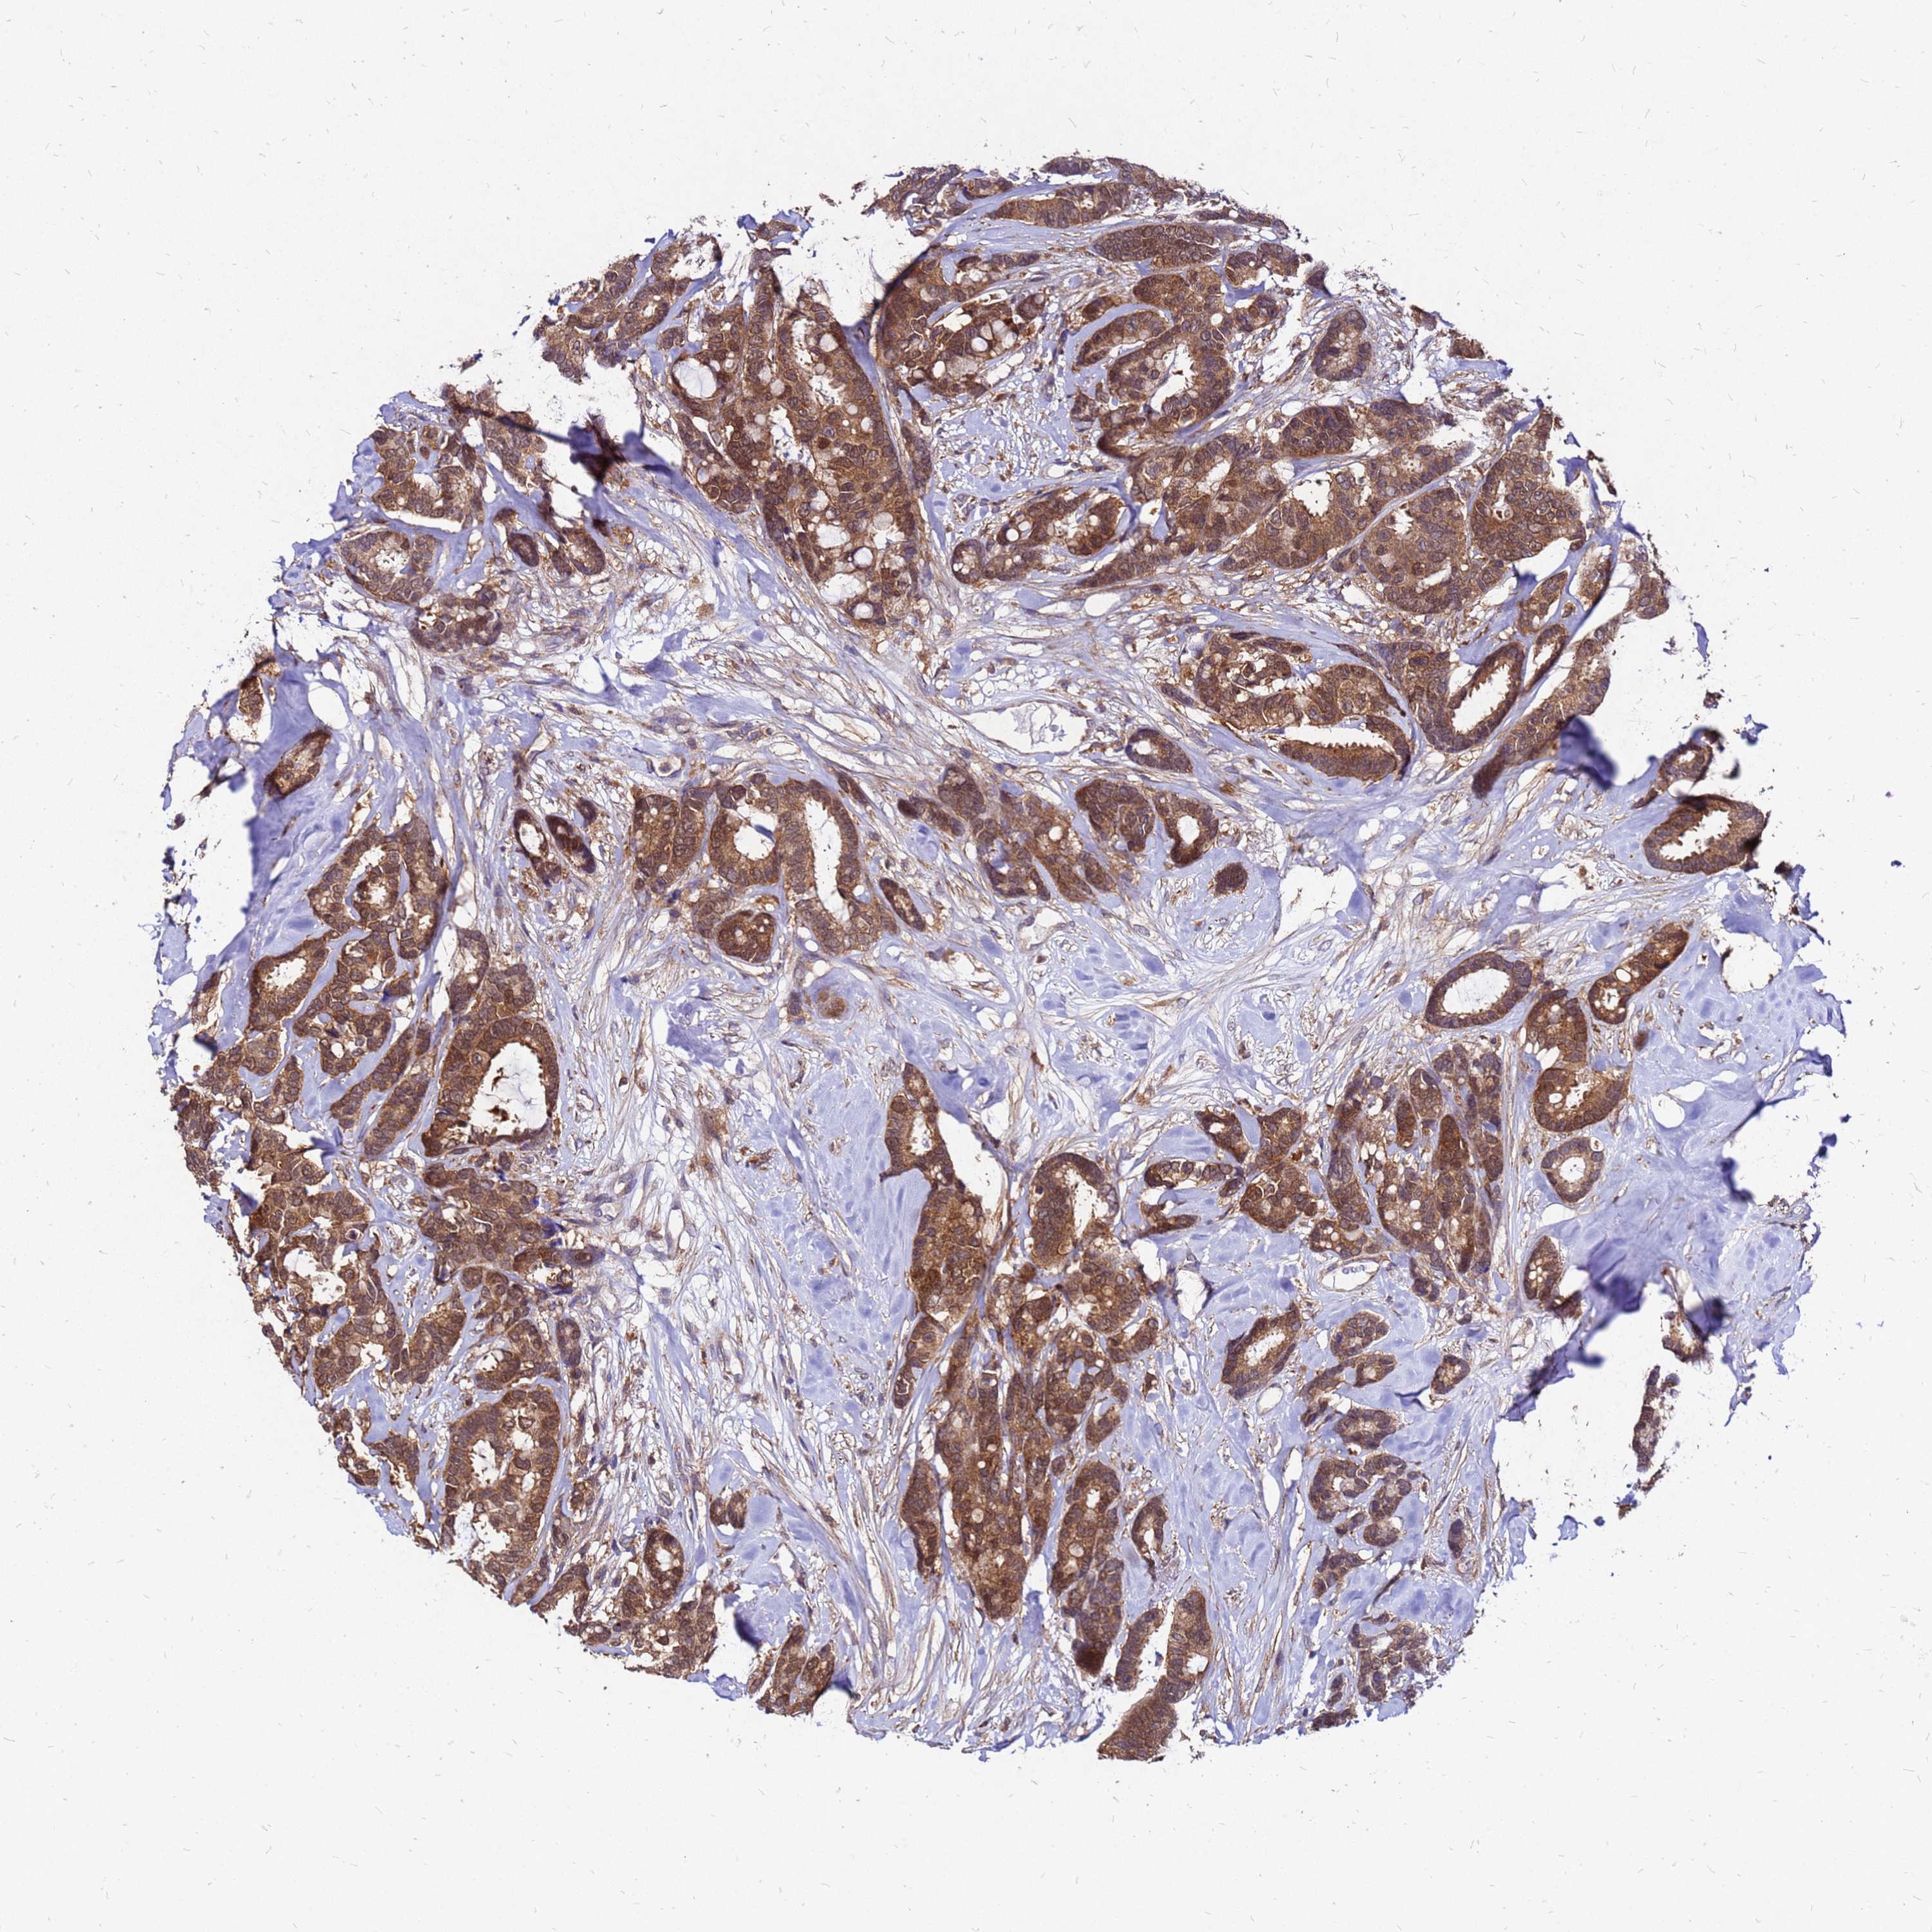

CANCER BREAST CANCER Show tissue menu

BRCA TCGA BRCA VALIDATION PROTEIN EXPRESSION

ANTIBODIES

AND

VALIDATION